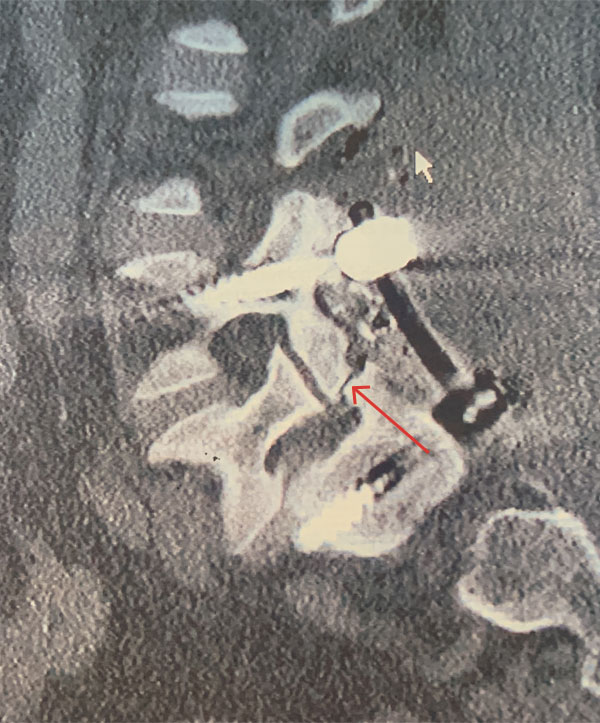

Figure 3 – Sagittal CT image showing post placement of posterior segmental fusion L4-S1 construct. Note pars deflect of L5 (arrow).